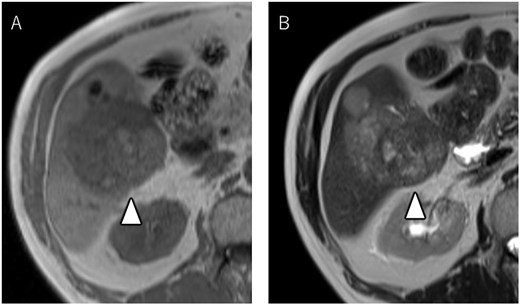

A 72-year-old man presented with abdominal pain. Computed tomography (CT) revealed a liver tumor in segment six/five, abutting the transverse colon without invading. Enlarged lymph nodes in regions 12b and 16b1 were noted, but there were no lung metastases or ascites. Magnetic resonance imaging revealed multiple nodular lesions in liver S6/5 with low signal intensity on T1-weighted images, and mosaic-like high signal intensity on T2-weighted images (Fig. 1). Based on these findings, the diagnosis of HCC was made, staged as cT2N1M1 Stage IVB. The patient underwent transarterial chemoembolization (TACE) followed by ATZ + BV therapy, resulting in tumor and lymph nodes reduction (Fig. 2).

Magnetic resonance imaging showing multiple nodular lesions in liver S6/5 with low signal intensity on T1-weighted images (A), and mosaic-like high signal intensity on T2-weighted images (B).